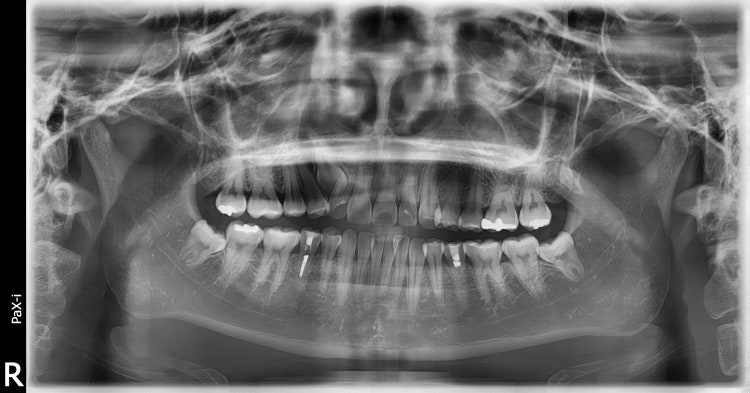

환자분과 방향이나 위치가 조금 다르지만 어쨌든 오른쪽 위 송곳니 매복인 성인 환자입니다.

환자분도 약간정도 있겠지만 이 환자는 중심선이 오른쪽으로 많이 틀어져 있고 교합이 약간 밀려들어가 있는 상태였습니다.

후방부(환자분의 경우도 사랑니를 뽑고 치아를 이동시켜줄 방향이죠)로 치아들을 이동시켜서 공간을 만들고 배열해 주었습니다.

CT를 찍고 방향을 잘 체크해서 내려보는 것이 가능하다면 자기 치아를 이용하면 더 좋기는 합니다. 그렇지만 시간이 오래걸릴수 있다는 것이 단점이 되겠습니다.